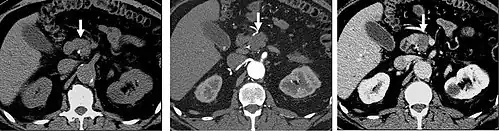

Detection and characterization of renal parenchymal masses is a frequent indication for CT. An initial noncontrast CT is important for detecting calcium or fat in a lesion, and to provide baseline attenuation of any renal masses. Following noncontrast scanning, intravenous contrast is injected and a corticomedullary phase is obtained at approximately 70 seconds (figure 7a, 7b). The corticomedullary phase is characterized by enhancement of the renal cortex as well as the renal vasculature. This phase is valuable in the evaluation of benign renal variants, lymphadenopathy and vasculature, however certain medullary renal masses may not be visible during this phase due to minimal enhancement of the medulla and collecting system. The parenchymal phase is obtained approximately 100–200 seconds after the injection of contrast material (figure 7c). Parenchymal phase imaging demonstrates continued enhancement of the cortex, enhancement of the medulla, and various levels of contrast material in the collecting system. The parenchymal phase is highly important for the detection and characterization of renal masses, parenchymal abnormalities, and the renal collecting system. This method of imaging does not evaluate for abnormalities of the collecting system.

FIGURE 7. Selected images from a renal mass specific protocol CT. Corticomedullary phase (axial 7a) demonstrates peripheral enhancement of the renal cortex with minimal opacification of the renal medulla. There is a large renal cell carcinoma in the left kidney (right in image) which can be differentiated from the normal renal parenchyma by the heterogeneous and differential enhancement. The renal artery and vein are opacified in this phase as well. The collecting system is not opacified (coronal reformat 7b). In the parenchymal phase, the renal cortex and the medulla are enhancing. The renal cell carcinoma in the left kidney is not as well defined when compared to the corticomedullary phase images, but is actually slightly more conspicuous. There is some contrast noted within the collecting system during this phase (7c).